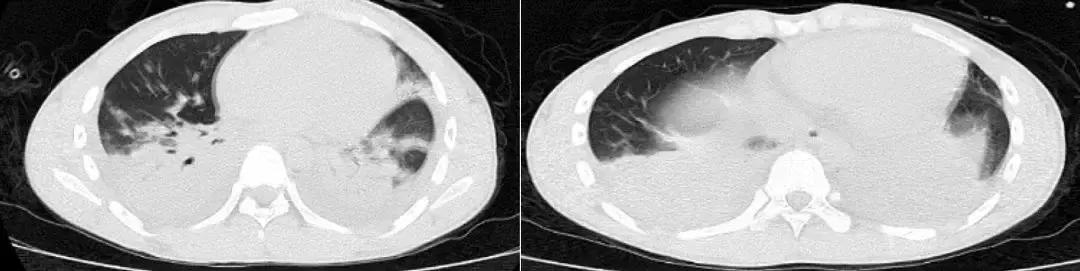

同年11月14日就诊于北京某三甲医院,查血常规:WBC 19.01×10^9/L ,N% 76.6%,ESR 25mm/h,PCT 2ng/ml。 血气分析(未吸氧):PH 7.514、PCO2 24.6mmHg、PO253.2mmHg、HCO3- 19.7mmol/L、BE -1.3mmol/L。 查胸部CT示:右肺上叶、中下叶、左肺下叶胸膜下片状实变影,可疑气管憩室。

肿瘤标记物:CA125 178.60U/ml、NSE 66ng/ml。风湿免疫:抗Ro-52抗体 弱阳性。PCT、ESR、G试验、GM试验正常。CRP :57.00mg/L。TB-SPOT:3.086 IU/ml。血气分析(2.5L/min):PH 7.48、 PCO2 31mmHg、PO2 73mmHg、HCO3- 25.3mmol/L、BE 0.5mmol/L、SO2 96%。 心梗四项:CK-MB 2.10ng/ml,Myo 39.74ng/ml;cTnI 0.017ng/ml;NT-proBNP 4599pg/ml。

患者肺部阴影明确,且逐渐进展,有支气管镜和经皮肺穿刺检查的指征,拟行支气管镜检查,在支气管镜检查之前因为患者未行术前检查,未能成功行支气管镜检查。

结局:11月22日超声心动图示:右房、右室扩大,右房内可见不规则等回声,附着于冠状静脉窦开口处,大小约31*12mm,随心动周期甩动;肺动脉高压,约85mmHg;三尖瓣反流(轻度);右室收缩功能减低,下腔静脉增宽;心包积液(少量)。

PET-CT提示宫颈占位,考虑肺栓塞与恶性肿瘤有关,可继续目前抗凝治疗,后来患者自动出院。

经验教训

靠近胸膜下楔形实变影,其底部宽基底于胸膜面,尖部指向肺门,呈驼峰征,提示栓塞动脉供血远端的肺实质出现肺梗死,约可见于30%的肺栓塞患者。长时间抗生素应用无效合并低氧血症的患者一定警惕肺栓塞。